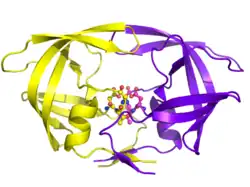

HIV-1 protease dimer in white and grey, with peptide substrate in black and active site aspartate side chains in red. (PDB: 1KJF) | |||||||||

Mature HIV protease exists as a 22 kDa homodimer, with each subunit made up of 99 amino acids.[1] A single active site lies between the identical subunits and has the characteristic Asp-Thr-Gly (Asp25, Thr26 and Gly27) catalytic triad sequence common to aspartic proteases.[8] As HIV-1 PR can only function as a dimer, the mature protease contains two Asp25 amino acids, one from each monomer, that act in conjunction with each other as the catalytic residues.[9] Additionally, HIV protease has two molecular "flaps" which move a distance of up to 7 Å when the enzyme becomes associated with a substrate.[10] This can be visualized with animations of the flaps opening and closing.